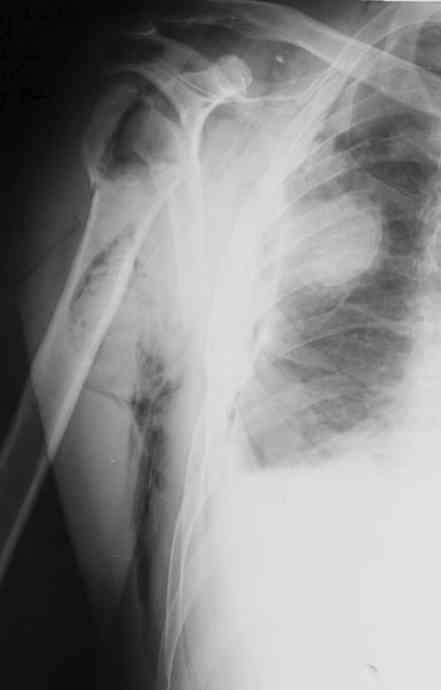

Я абсолютно согласен с Вами. Бугорки мы не выделяли и не фиксировали. Дело в том, что основная линия перелома проходит по анатомической шейке. И ниже нее кость повреждена, но существенного смещения осколков и бугорков до и во время операции не отмечено (прилагаю первичный снимок лучшего качества - рис. 1).

Интраоперационно было установлено, что осколки находятся примерно на своих местах и плотно связаны с окружающими тканями. Мы не стали их выделять, мобилизировать и фиксировать, так как это все равно будет необходимо сделать при установке эндопротеза.